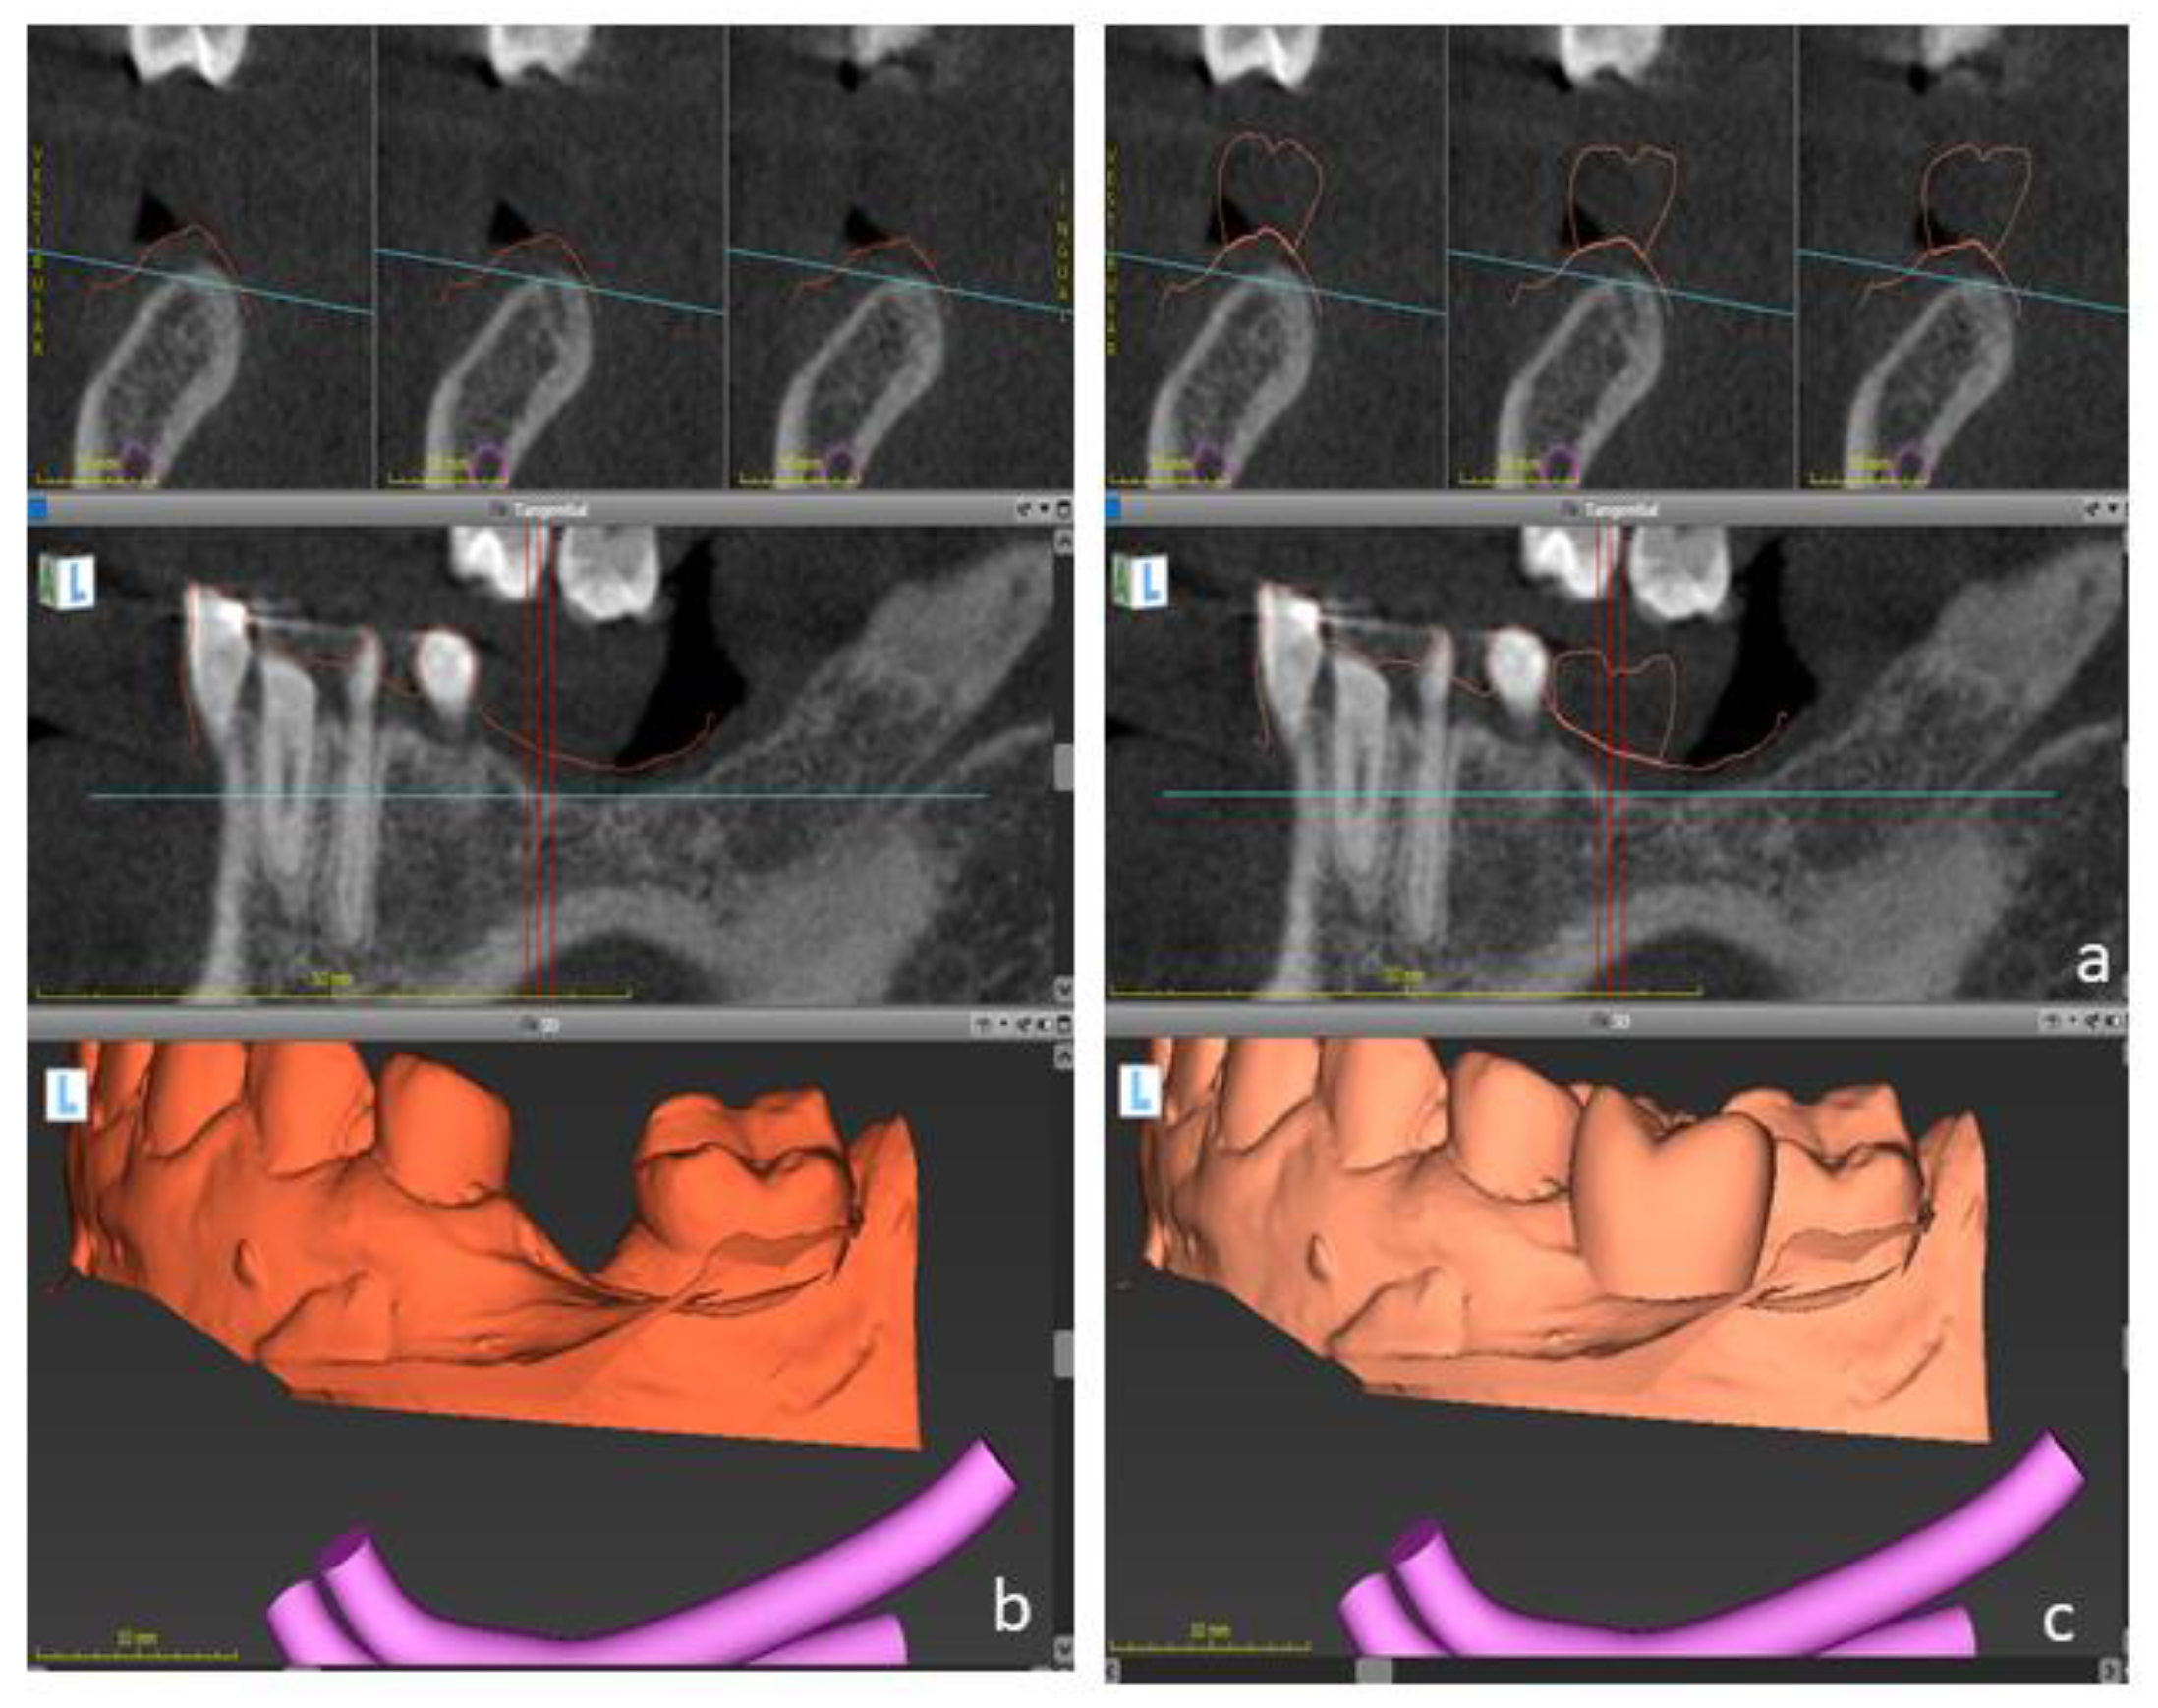

Figure 8.

Dental implant planning on lower jaw. Sagittal cuts of cone-beam computed tomography (DICOM files) are shown (a). DICOM files were superimposed to the intraoral casts (b) and to the digital wax-up (c) to determine the optimal implant position.

Figure 9.

Design of a surgical guide to be used as a reference to dental implant placement.